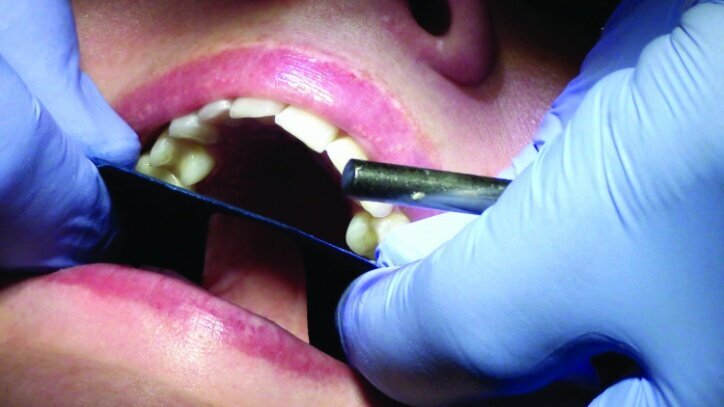

Depth guide cuts were made using a 330 bur, which has a 2 mm cutting surface (Figs. 2a–3b). This ensures 2 mm of occlusal reduction to accommodate 2 mm of material thickness on the occlusal surface of the restoration.

Gross occlusal reduction was completed using a KS7 bur to the depth cuts (Figs. 4–8b, 9c). Adequate clearance was verified with a 2 mm prep check from Common Sense Dental Products.

After gross occlusal reduction was completed, the remaining enamel ring was measured (Figs. 9a, b). The enamel rings were noted to be 1.5 mm, and the teeth were prepared for adhesively retained restorations. If the enamel rings were less than 1 mm, the teeth would have been prepared on the axial walls to create retention for cohesively retained crowns.